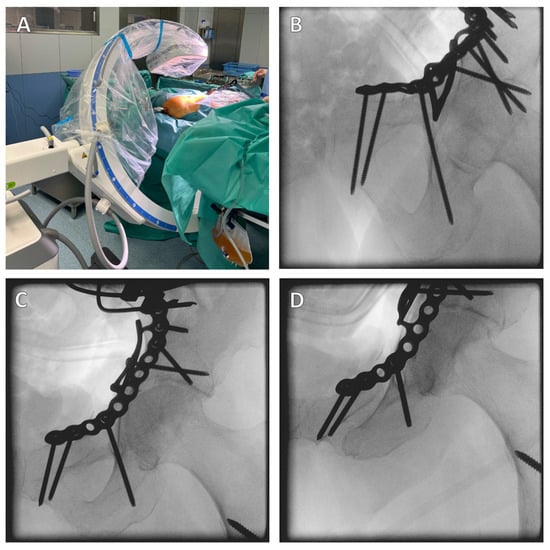

For the modified Stoppa approach, the patient is placed in the supine position with the hands extended on either side of the body (Figure 4A). Due to the positioning, the X-ray image converter can be used intraoperatively for the standard anterior–posterior (AP), ala, and obturator images, and, depending on the inclination of the image converter, allows the examination of screws positioned next to the joint [27]. After sterile covering of the patient, a Pfannenstil incision is made, although vertical incisions are also possible. The difference between the incisions is currently the subject of scientific discussion, with a vertical incision being associated with a lower infection rate [42,43].

The correct position of the screws should be checked intraoperatively by X-ray control in the ala/obturator and AP view, which confirms the extra-articular position of the screws (Figure 6). The infra-acetabular screw can be scored in its extra-articular position, confirming the correct position outside the hip joint. Postoperatively, the correct position should be confirmed by CT.

Open reduction and internal fixation (ORIF) of the acetabular fracture is then performed. The correct position of the screws is checked intraoperatively using an X-ray C-arm (Figure 6).

Figure 6. Intraoperative X-ray control. It is important to position the patient correctly; a carbon table should be used, and this should be moved out as far as possible so that there is plenty of space to swivel the X-ray C-arm (A). The correct screw position is checked in different planes. Here, the infra-acetabular screw is in the correct position, i.e., not through the joint (BD).